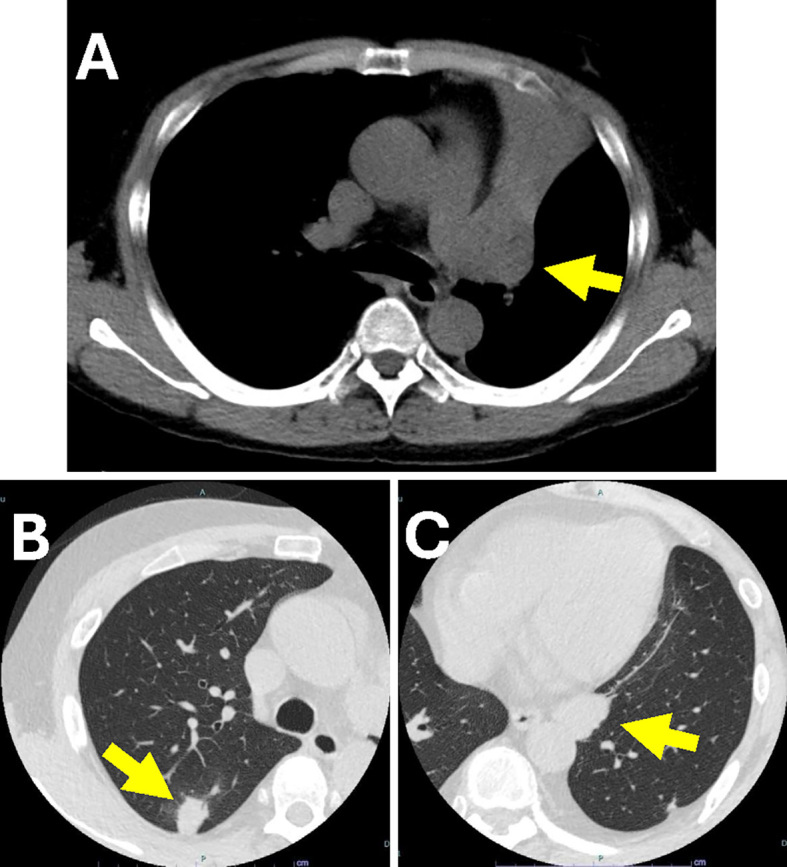

移植后淋巴细胞增生性疾病(PTLD)影响0.8-2.5%的肾移植患者,发病率在移植后1年和10-14年达到高峰。非常晚发性PTLD (VL-PTLD)可在移植后10年以上发生,据报道可达30年,但其特征尚不清楚。61岁男性,肾移植45年后出现PTLD,表现为发热、呼吸急促。计算机断层扫描显示肺和肝脏肿块,活检证实为IVB期单纯性PTLD。尽管获得了初步改善,但患者于第66天死亡。VL-PTLD可能不同于早发性或晚发性PTLD,因此需要进一步研究相关风险和管理。

Post-transplant lymphoproliferative disorder (PTLD) affects from 0.8-2.5% of kidney transplant patients, with peaks in incidence within 1 year and 10-14 years post-transplant. Very late-onset PTLD (VL-PTLD) can occur over 10 years post-transplant, reportedly up to 30 years, but its characteristics remain unclear. A 61-year-old man developed PTLD 45 years after kidney transplant, presenting with fever and shortness of breath. Computed tomography revealed lung and liver masses and biopsy-confirmed stage IVB monomorphic PTLD. Despite obtaining an initial improvement, the patient died on day 66. VL-PTLD may differ from early- or late-onset PTLD, thus necessitating further research on both the associated risks and management.